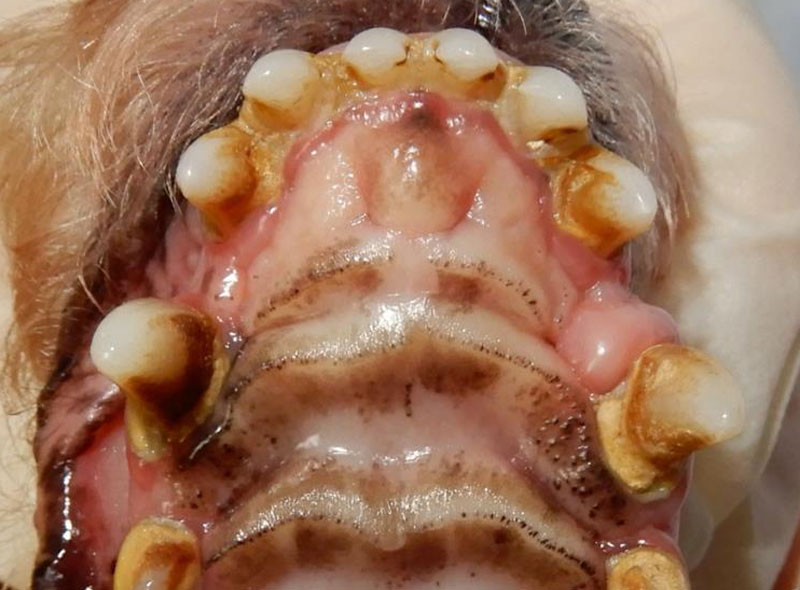

口腔疾患

歯周病(歯肉炎&歯周炎)

-

側面から

正面から

写真は重症例です。

歯周病は、見た目で分かりますので、発見のしやすい病気です。

歯肉炎→歯周炎と進行します。